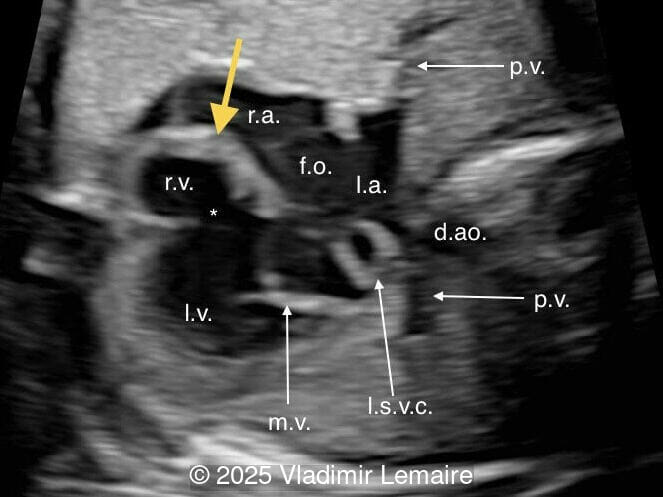

We present a case of isolated tricuspid atresia type 1 with persistent left superior vena cava. No other extracardiac anomalies were found. Our diagnosis was confirmed after birth.

In the images below, the abbreviations are as follows: RA: right atrium; RV: right ventricle; LV: left ventricle; MV: mitral valve; LA: left atrium; FO: foramen ovale; SVC: superior vena cava; LSVC: left superior vena cava; PV: pulmonary veins; PA: pulmonary artery; MPA: main pulmonary artery; RPA: right pulmonary artery; AO: aorta; dAO: descending aorta; aAO: ascending aorta; DA: ductus arteriosus; T: trachea; * marks the ventricular septal defect.

Basal four-chamber view. Note the presence of an atretic tricuspid valve (yellow arrow) as well as a ventricular septal defect (*).

Image 1 Basal four-chamber view. Note the presence of an atretic tricuspid valve (yellow arrow) as well as a ventricular septal defect (*).

Four-chamber view with color Doppler. Color Doppler confirms the absence of blood flow across the tricuspid valve in diastole.

Image 2 Four-chamber view with color Doppler. Color Doppler confirms the absence of blood flow across the tricuspid valve in diastole.

Tricuspid atresia is a rare anomaly, with an incidence of 0.08 per 1,000 live births, and is characterized by the lack of communication between the right atrium and ventricle. As a result, the right ventricle is hypoplastic. The tricuspid valve apparatus does not develop in the majority of cases, and the right atrioventricular junction appears as echogenic thickened tissue on ultrasound examination. An inlet type ventricular septal defect is always present, and the size of the right ventricle depends on the size of the ventricular septal defect. As a consequence of the obstructed tricuspid valve, a large interatrial communication, in the form of a widely patent foramen ovale or atrial septal defect, is necessary.

The four-chamber view in tricuspid atresia is diagnostic. It reveals a small right ventricle, a ventricular septal defect, and the absence of a right-sided atrioventricular junction. The size of the right ventricle mainly depends on the size of the ventricular septal defect: the smaller the ventricular septal defect, the smaller the right ventricle. Its contractility is normal with no myocardial thickening. The atretic tricuspid valve appears as echogenic thickened tissue and the right atrium is slightly dilated. The interatrial communication is large and there is often a redundant flap of the septum secundum that bulges into the left atrium. The interatrial and interventricular septa are malaligned.

Color Doppler confirms the diagnosis on grayscale ultrasound, as it demonstrates the lack of blood flow across the tricuspid valve and a patent mitral valve. Due to increased blood flow across the mitral valve, aliasing is typically noted on color Doppler. Mitral valve regurgitation has been associated with a poor outcome. The right ventricular cavity is filled in late diastole from the left ventricle, through the ventricular septal defect. Left-to-right shunting across the ventricular septal defect can be seen on color Doppler. Color Doppler is helpful in the evaluation of flow across the great arteries. Flow across the pulmonary artery is generally antegrade. Pulmonary stenosis should be suspected when the vessel is diminutive in size rather than the demonstration of turbulent flow on color Doppler, which is typically absent in these cases.